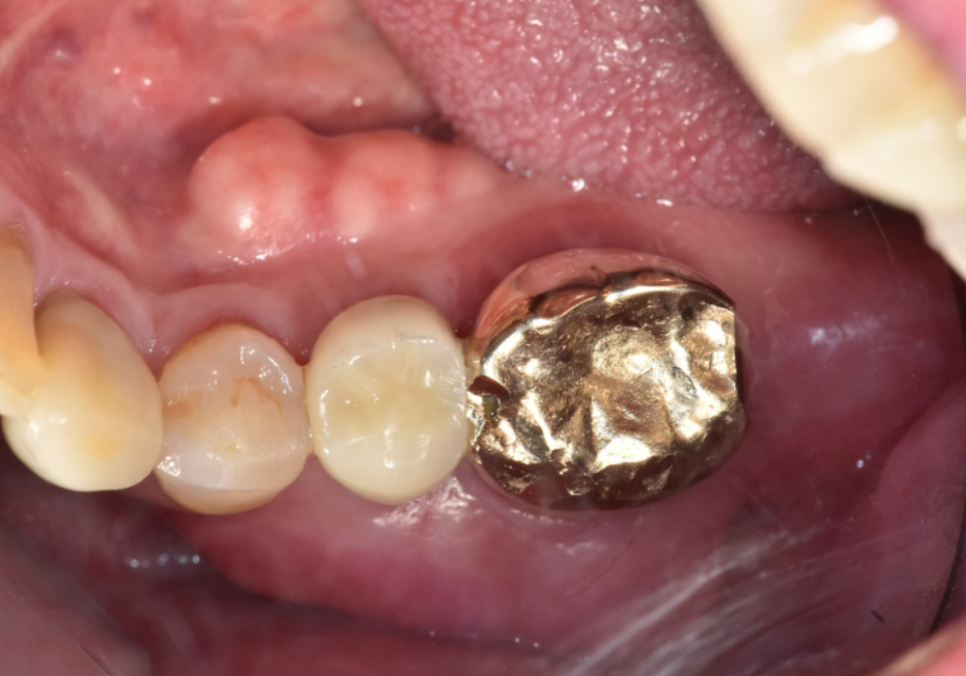

두 번째 사례, 8개월 뒤 다른 금니가 또 빠진 환자분

상일역 치과, 오래된 금니 빠짐

임플란트 치료가 잘 끝나고 8개월 뒤...

환자분께서 또다시 저희 병원을

내원하셨습니다.

250822

이번엔 반대쪽인

왼쪽 아래 어금니인 금니가

'툭' 하고 빠지신 건데요.

지난번 발치의 아픈 기억 때문인지,

"이번에도 뽑아야 하나요...?"

하며 걱정이 태산 같으신 모습이었습니다.

조심스럽게 빠진 자리를 살펴보니,

역시나 치아 내부에

까맣게 충치가 진행되어 있었죠.

하지만..

엑스레이와 구강 상태를 꼼꼼히 확인해 보니,

이번 치아는 다행히

발치 없이 충분히 살려서 쓸 수 있는 상태였습니다.

이번 케이스가 지난번과 달랐던 결정적인 차이,

바로 금니 표면의 '구멍' 유무였습니다.